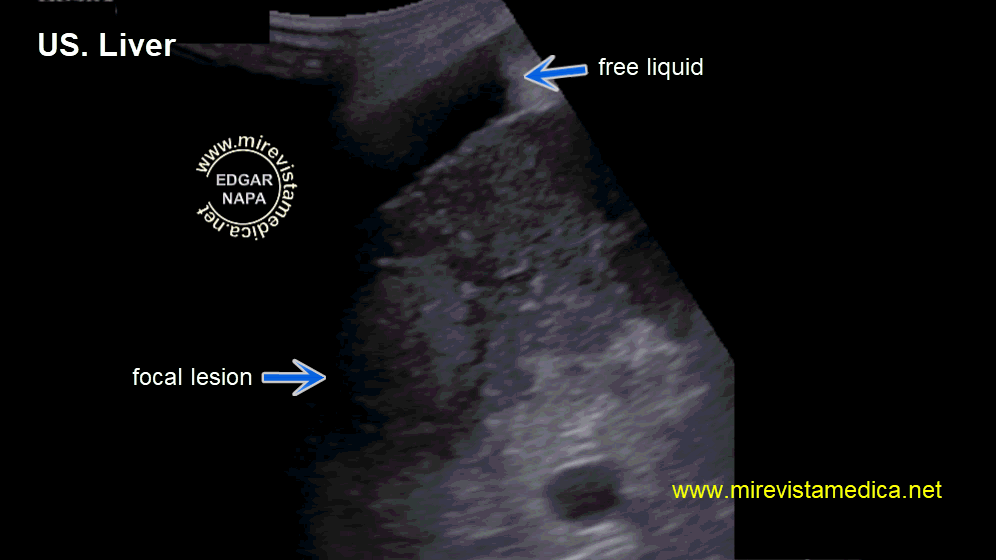

Semiología de los conductos intra y extrahepáticos en ultrasonido